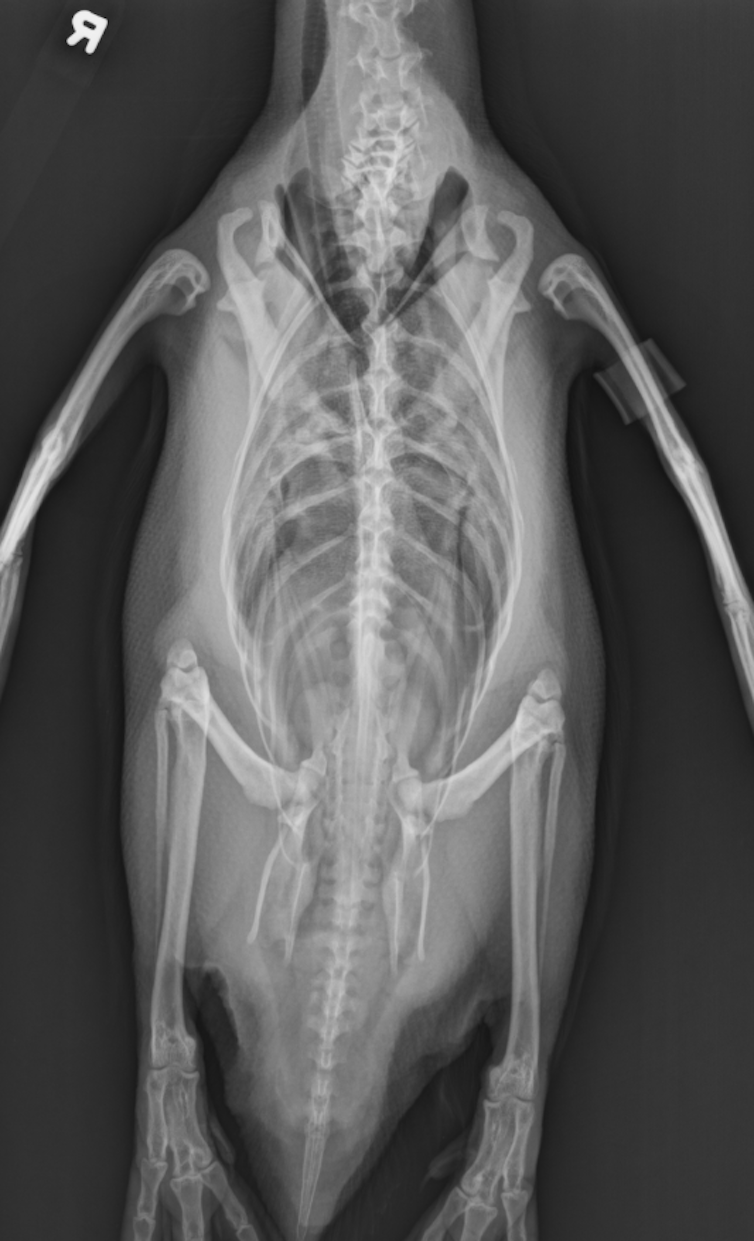

I’m always fascinated when I have to take X-rays of an injured bird that might have a broken bone, is sick or having difficulty moving. While penguins might look like simple, torpedo-shaped ice-waddlers, their bodies are actually quite complex.

Even though they look nothing like people or animals you may encounter every day – like dogs and cats – they have similar skeletons and joints. They even have knees and elbows, but have about half as many bones. A human skeleton is made up of 206 bones. A penguin has just 112 in its whole body.

Birds also have fewer bones in their spines than many animals. Their lower back bones joined together into just one bone, called the synsacrum. The only other animals to have this type of backbone were the dinosaurs. For the birds, this helps them keep their bodies in a horizontal position without tiring out their back muscles while flying or swimming.

Penguins developed dense, hefty bones that don’t have the air pockets that flying birds have. That helped make up for the air sacs around their lungs. Their bulky bones keep them from floating up to the water’s surface, like a scuba diver who straps on a weight belt to submerge.

Penguins’ wings are also different because these birds need to swim, not soar into the sky. Penguins’ wings morphed into what look like short, flat, stiff fins that don’t bend like flying birds’ do. They also have fewer bones than other birds.